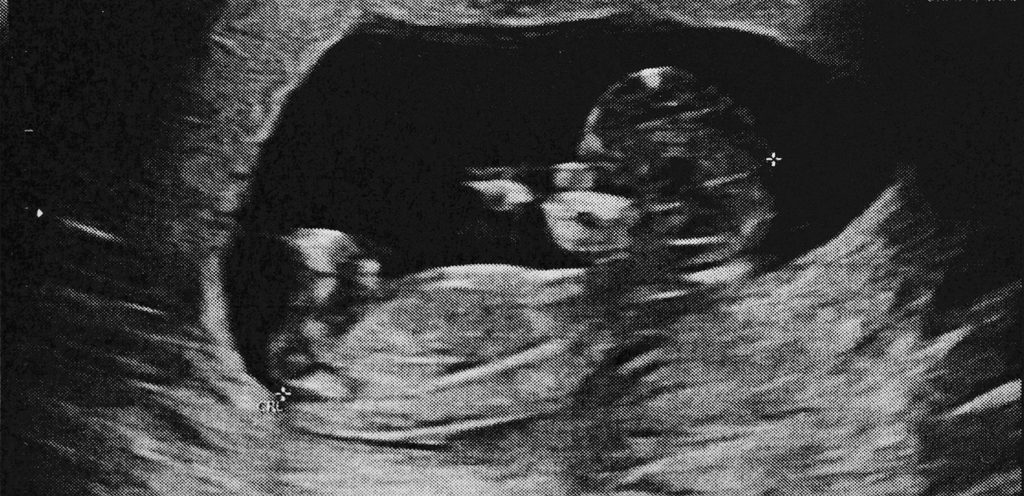

في الشهر التاسع من الحمل، يكون حجم وسماكة المشيمة بلغ ذروته بين سنتمتران وأربعة سنتميترات. وتكون قادرة على أداء وظائفها بشكل مثالي. ويكون موقع المشيمة في الحالات الطبيعيّة في الجزء العلوي أو الجانبي من الرحم. لحين الولادة، حيث تخرج المشيمة من رحم الأم بعد خروج الطفل وحدها كإحدى مراحل الولادة، أو يقوم الطبيب باخراجها.